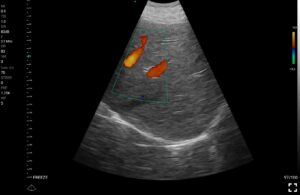

Παραδείγματα

Ολες οι παραπάνω απεικονιστικές εξετάσεις έχουν ληφθεί από φορητή συσκευή όπως: Apple Iphone, Tablet, Samsung Mobile Phones και διάφορες άλλες φορητές συσκευές.